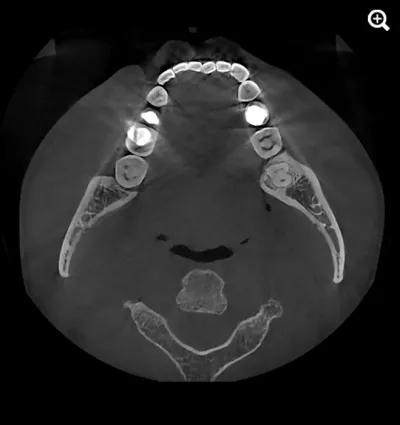

When capturing a CBCT scan, the presence of metal in the oral cavity can introduce artifacts, shadows, and bright streaks that significantly compromise image quality. These distortions may obscure critical anatomical structures, making it more difficult to evaluate bone integrity and surrounding areas—adding complexity to diagnosis and increasing clinical stress.

HDX WILL’s cutting-edge technology now offers a powerful solution through PrecisionMAR™, a metal artifact reduction feature that enhances clarity and ensures more precise imaging—even around metal. This is especially valuable for both dental professionals and ENT specialists focused on comprehensive treatment planning, including airway-focused care.

Minimizes scatter for cleaner imaging

Reduces shading and streak-related artifacts

Clearly defines bone and dental structures adjacent to metal

With improved image fidelity, practitioners can more confidently diagnose conditions, plan treatments, and support airway health initiatives critical to both dental and ENT fields.